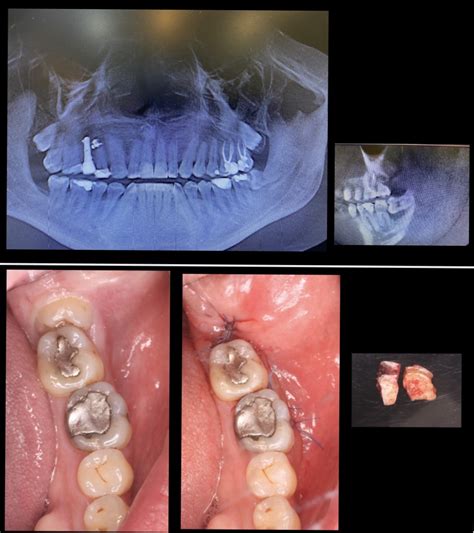

Una vez que la anestesia hace efecto, el cirujano oral, con ayuda de instrumentos específicos, procede a extraer la muela, ya sea entera o fragmentada en piezas más pequeñas para simplificar la extracción.

En la mayoría de los casos, este procedimiento es bastante directo y se completa en solo unos minutos. Aún así, cabe señalar que, dependiendo de cómo esté posicionada la muela, el proceso de extracción puede ser diferente.

- Extracción simple: Se realiza cuando la corona de la muela del juicio ha erupcionado completamente de la encía. Este procedimiento es rápido y generalmente se realiza bajo anestesia local.

- Extracción quirúrgica: La cirugía de extracción de muela del juicio se lleva a cabo cuando está retenida o parcialmente erupcionada. Durante la operación, el cirujano debe hacer una incisión en la encía para acceder al diente (a veces dividiéndolo en secciones para facilitar su extracción).